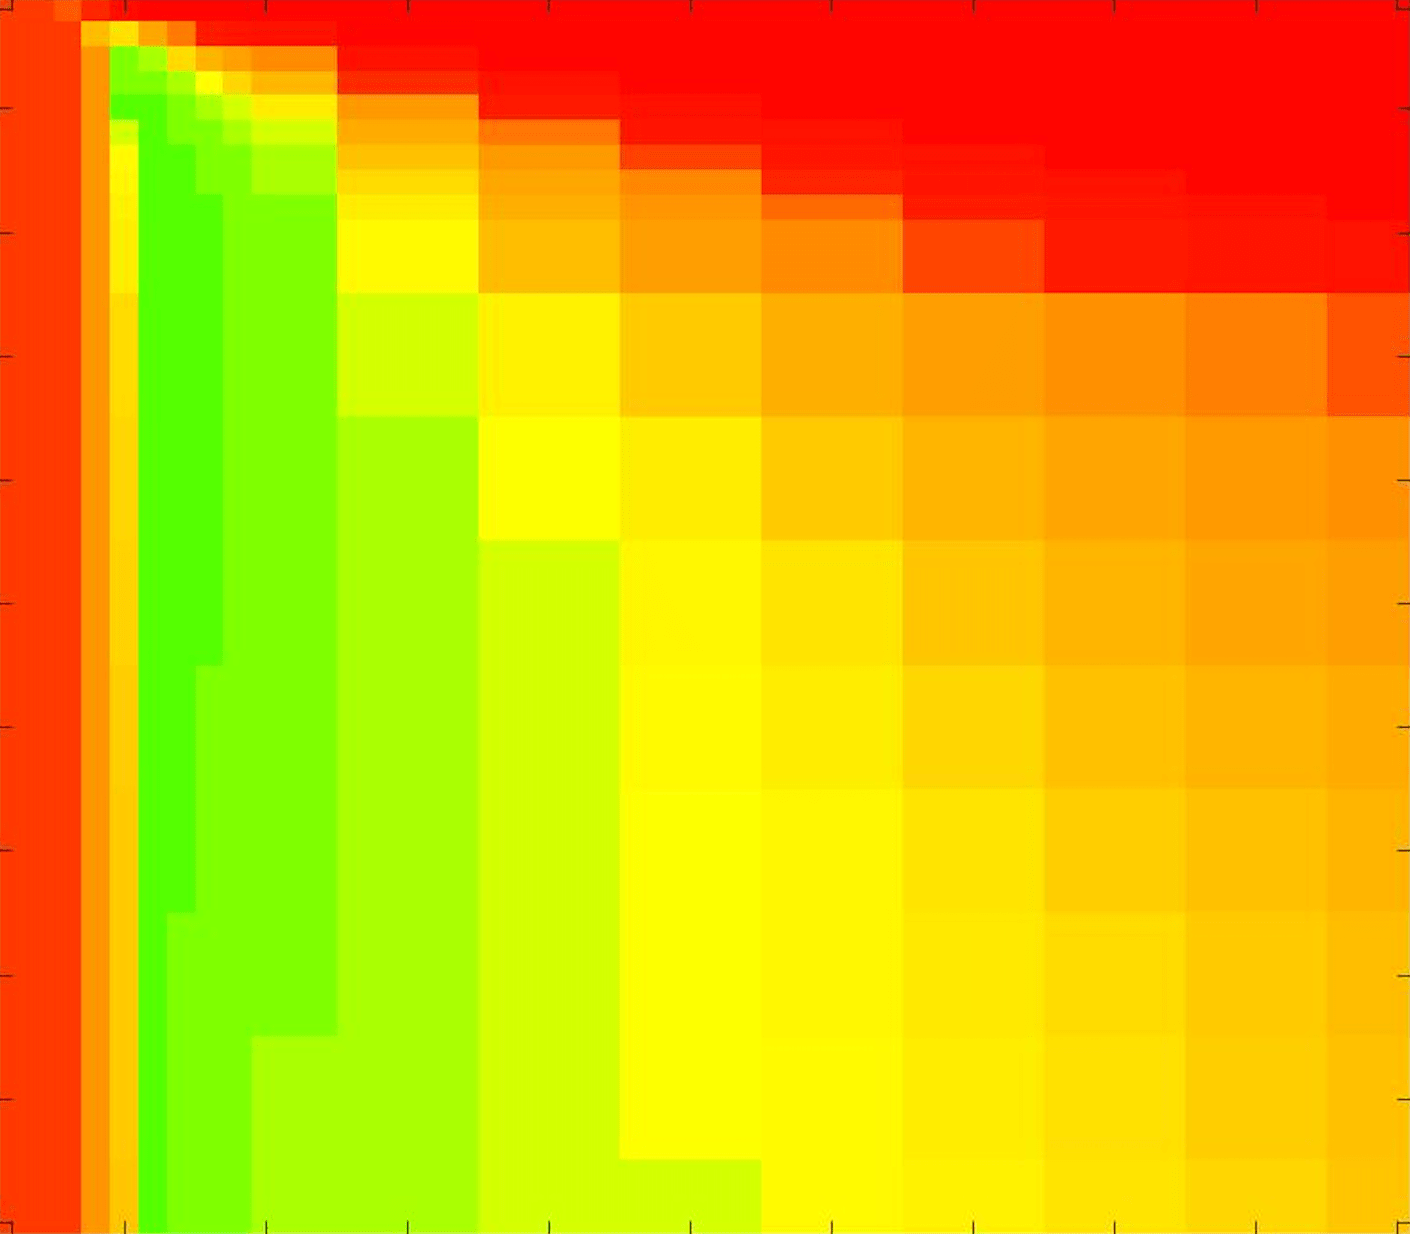

where refers to the number of points in the enclosed region. This takes values in the range , with higher TC values indicating a more accurate segmentation. In the following we will represent accuracy visually from red () to green (), with the intermediate scaling of colours used shown in Fig. 8. This will be particularly relevant in §7.2.

The TC values for the parameter sets are presented as heatmaps in Figs. 11–13. A heatmap is a convenient way to display accuracy results for hundreds of tests concisely. In Fig. 9 we give an example heatmap with the same axes used for those in Figs. 11–13. For each of the combinations of parameter values we give the TC value of the segmentation result and represent it by the appropriate colour. The corresponding colour scale is shown in Fig. 8. Qualitatively, the more green areas of the heatmap the more accurate the model is for a wider set of parameters. Example results for Test Image 5 when varying (with ) for the proposed model are given in Fig. 10. Here it can be seen what each accuracy result corresponds to visually.

Note. The axes have been removed from the heatmaps in Figs. 11–13 for presentational clarity. However, to be explicit, the axes used in all heatmaps are the same as those in Fig. 9.

Synthetic Images. These results are presented in Fig. 11. For Test Images 1–2 we see poor parameter robustness from all competing models, except for GAV which performs reasonably well. However, the proposed model has minimal parameter sensitivity for these images, with good results achieved for almost every combination of values tested. For Test Image 3 all models have a reasonable parameter range (except for RSF), however the proposed model gives better quality results for a wider parameter range. The other models achieve reasonable results here as the foreground intensity of the ground truth is greater than the background , whereas for Test Images 1–2 they are equal . These results highlight the key advantage of the proposed model.

Real Images. In Fig 12 we present results for Test Images 4–6. Here, the proposed model performs in a similar way to its competitors because these images are more typical selective segmentation problems in the sense that there is a clear distinction between the foreground and background intensities. In particular, the values in each case are: Test Image 4 , Test Image 5 , and Test Image 6 . It can be seen that the proposed model is competitive compared to previous approaches. The performance is quite poor for Test Image 5, but is arguably still the best for this challenging case. In Fig. 13 we present results for Test Images 7–9. Here the proposed model outperforms previous approaches significantly for each image. This is mainly due to the type of image considered. Specifically, the true intensities are: Test Image 7 , Test Image 8 , and Test Image 9 . The proposed model is capable of achieving results where , with other models failing completely in these cases.